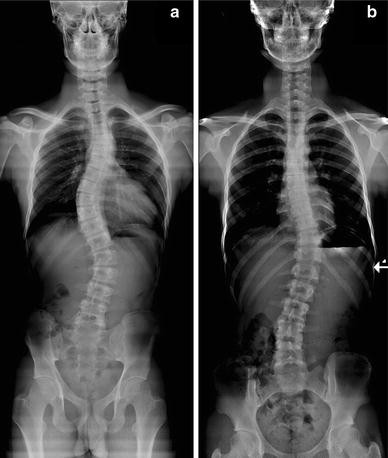

진단하고 치료함에 있어서 아주 많은 정보를 얻을 수 있습니다. 단지 병소 부위만을 확인하는 게 아니라, 구조적 배열상태나 연부조직의 상태 등 많은 것을 알 수 있습니다. 내원하시는 분들이 잘 이해할 수 있게 자세한 설명도 들을 수 있습니다^^.